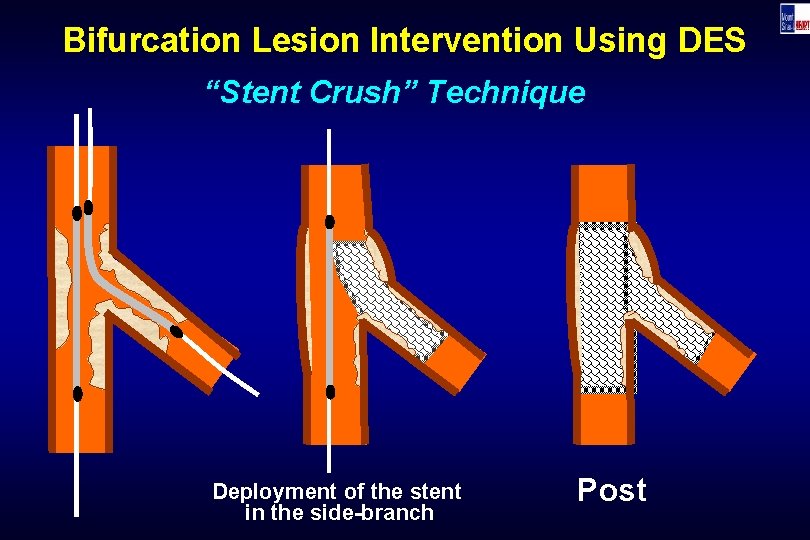

Bifurcation Lesion Intervention Using DES “Stent Crush” Technique Deployment of the stent in the side-branch Post